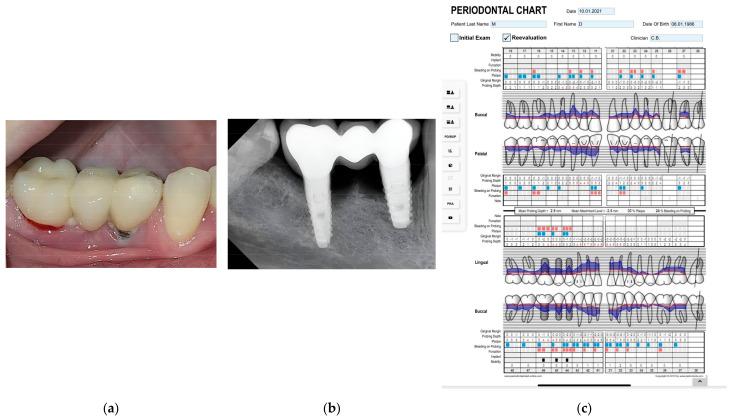

We followed 40 patients, with a total number of 92 dental implants, divided into three age groups: under 35 years, between 35 and 55 years, and older than 55 years. Patients were also divided into groups according to the time since implant placement: 1-3 years, 4-7 years, and more than 7 years. The patients were examined, and periodontal pocket depth, peri-implant pocket depth, Löe-Silness gingival index, mucosal thickness, and keratinized mucosal width were recorded; bone resorption was measured on radiographs using a 2D image analysis method; and a questionnaire was also conducted.

我们跟踪了40例患者,共92颗牙种植体,分为三个年龄组:35岁以下、35至55岁、55岁以上。患者还根据种植体植入后的时间分组:1至3年、4至7年、7年以上。对患者进行检查,记录牙周袋深度、种植体周围袋深度、洛 - 西伦牙龈指数、黏膜厚度和角化黏膜宽度;使用二维图像分析方法在X线片上测量骨吸收情况;并进行问卷调查。